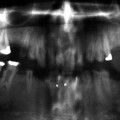

The exact number of developmental defects is not known, but it certainly is in the hundreds with new conditions still being described in the literature. For example, a newly described condition that affects the first permanent molar and sometimes permanent incisors (molar incisor malformation – MIM) has just recently been described for the first time [15, 34]. The first permanent molars have a thin pulp chamber and abnormal root formation, and the etiology and prevalence are unknown at this time (Fig. 1.1). There are many known hereditary and environmental conditions associated with abnormalities in tooth number (both too many and too few). The medical history, in some cases, will readily provide the cause for missing teeth, such as a child received extensive head and neck radiation and/or chemotherapy for cancer while the dentition was in its early developmental stages [8]. In other cases, the etiology will be more elusive as there may be a noncontributory medical history and no family history of missing teeth. As will be discussed in Chaps.​ 3 and 4, congenitally missing teeth can be associated with a syndromic condition, or it can occur as a nonsyndromic condition.

A314832_1_En_1_Fig1_HTML.jpg

Fig. 1.1

The molar malformation that is referred to as molar incisor malformation is readily evident in this panoramic radiograph that shows the second primary and first permanent molars and maxillary permanent incisors are all affected